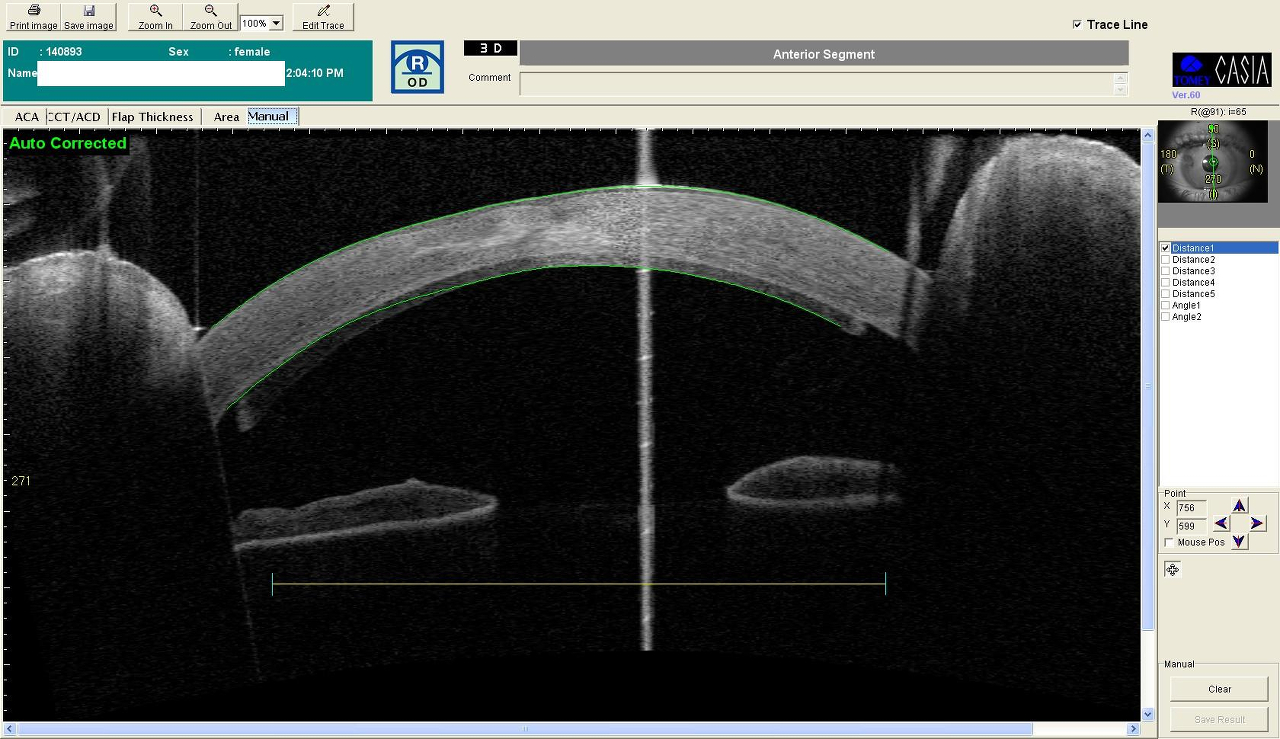

4 CHED (distrofia endoteliale ereditaria congenita)

Paziente di 16 anni con visus <1/10 cc (vecchi referti di visite oculistiche con visus di 5/10) peggiorato negli anni. Cornea opalescente di spessore molto aumentato (1100 micron circa). Posta diagnosi di CHED (distrofia endoteliale ereditaria congenita) con successivo trapianto endoteliale (DSAEK) in maggio 2011 in od.

Attualmente la cornea nell’occhio destro è trasparente e il visus è di 5/10 cc.